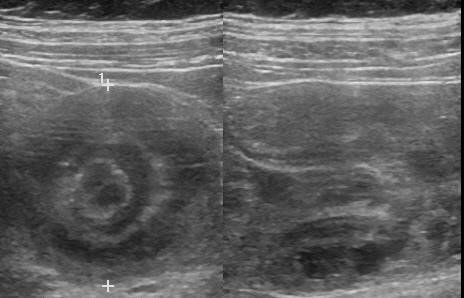

A ultrassonografia é uma modalidade de exame muito efetivo e confiável para a demonstração da intussuscepção. Caracteristicamente, uma massa cilíndrica é observada, consistindo em um anel hipoecoico externo que circunda tecidos com ecogenicidade variável e representam as camadas do intestino edemaciadas que se alternam com camadas do mesentério conhecido como “sinal do alvo”. Outros sinais incluem sinal de donut e pseudo-rim. A ultrassonografia com Doppler tem sido utilizada para estimar a viabilidade do tecido.